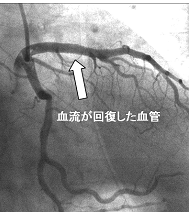

狭かった部分が前後と変わりなくきれいに広がっています。

現在は風船治療のみで終了する場合は少なく、再狭窄(広げた部位が再度狭くなること)を防ぐ目的でステント(細い金網の筒)を入れることが多くなっています。とくに、治療した部分での細胞の増殖を抑える薬剤を塗った薬剤溶出性ステントを用いた場合の再狭窄率は10%以下と、良好な成績をあげています。

この患者さんは、カテーテル治療により今まで悩まされていた胸の痛みから解放されました。